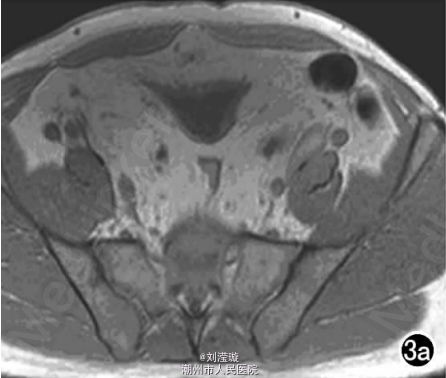

腹部B超示双肾增大,双肾慢性肾病声像;双肾中度积液伴双输尿管上段扩张。 IVPshi双侧输尿管中或下段梗阻。 膀胱造影:经尿道置管后,注射对比剂充盈膀胱,膀胱下半部先充盈,继续灌注对比剂后见膀胱完全显影,膀胱形态异常,呈“倒葫芦状”(图1)。 CT增强扫描行延迟期 MPR重组,见双侧肾盂、肾盏扩张积液;双侧输尿管纡曲、扩张,下端呈鸟嘴样变窄;膀胱变形、体积减小(图2); MRI平扫示双侧肾盂、肾盏扩张积液,双侧输尿管扩张并下端鸟嘴样变窄,盆腔内多量脂肪沉积,分布于膀胱、直肠周围,T1WI、T2WI呈明显高信号,T2WI抑脂像呈稍高信号,膀胱受压变形、体积减小(图3a~c); MRU示双侧肾盂肾盏扩张、积液,双侧输尿管显著纡曲、扩张,下端鸟嘴样变窄,管壁光整,膀胱变形、体积较小、位置抬高(图3d)。

综合影像资料,该例符合盆腔脂肪增多症典型改变。 于全麻下行剖腹探查术,适当清除双侧输尿管周围、膀胱周围及腹膜后脂肪,离断双侧输尿管下段后行输尿管膀胱再植术。取活检病理结果为纤维脂肪组织。